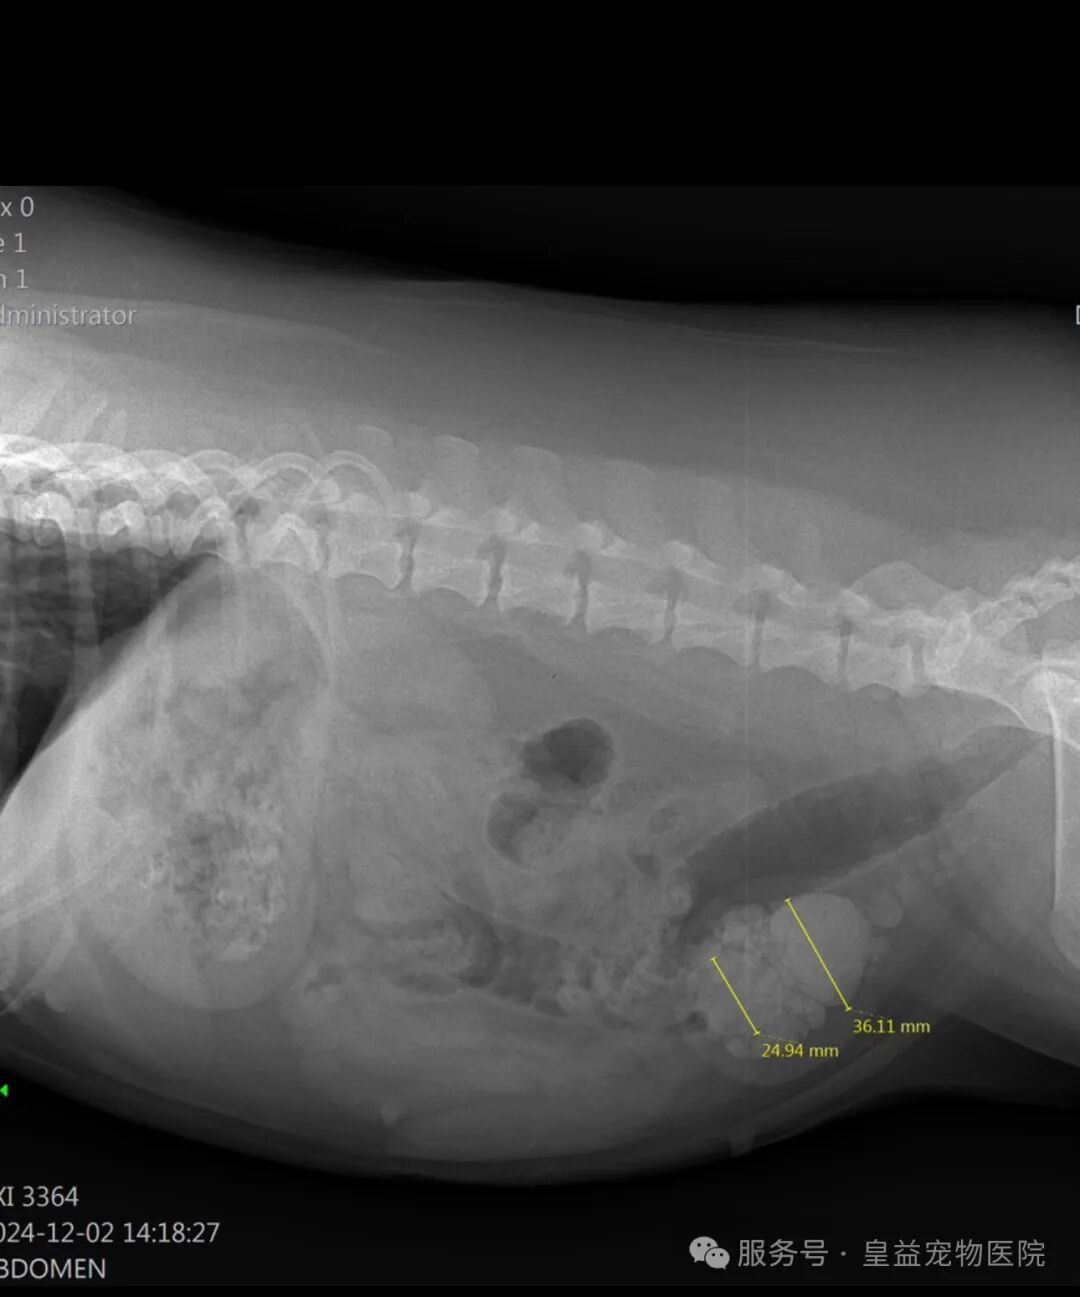

- B超/X光:排查结石、膀胱壁增厚